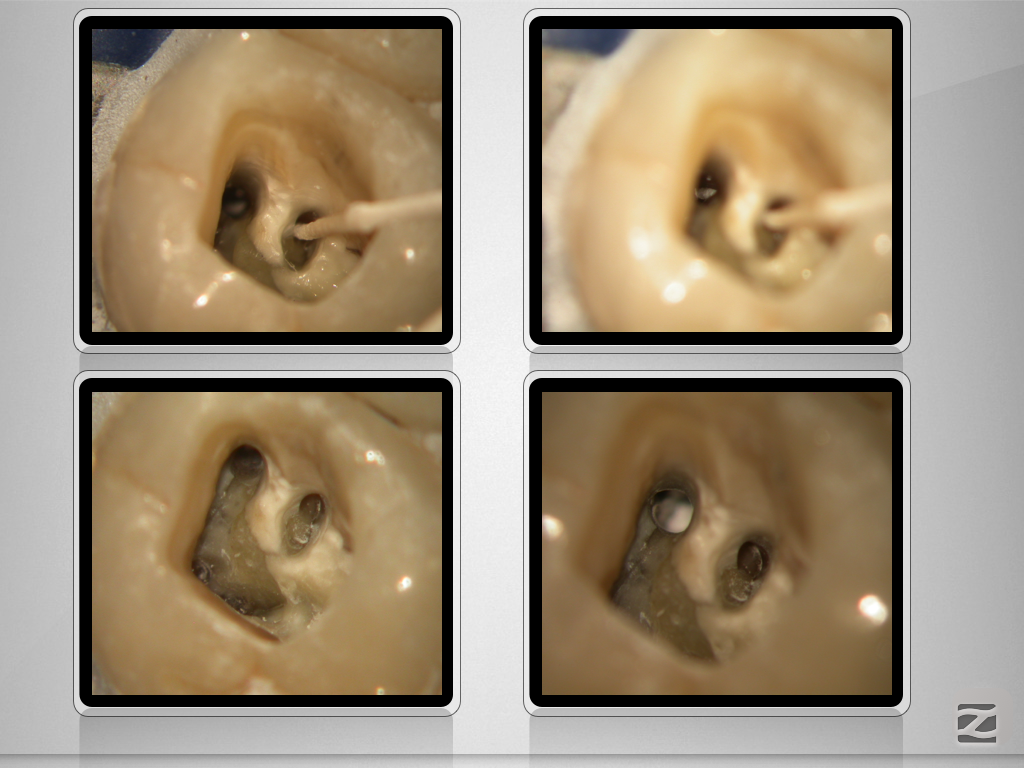

26D.011

X-Bein